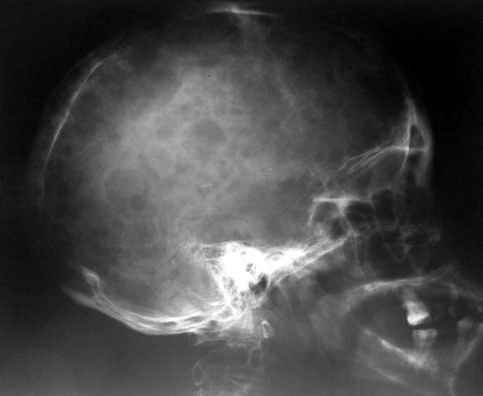

половиной нижних поясничных позвонков и проксимальной части бедренной кости. Другими словами, в редких случаях

объем изменений совсем не возрастает по направлению к.периферии. В самых редких случаях в какой-то ничтожной

степени в процесс может быть вовлечен череп (часть нижней челюсти). Поражения ребер мы ни разу не наблюдали.